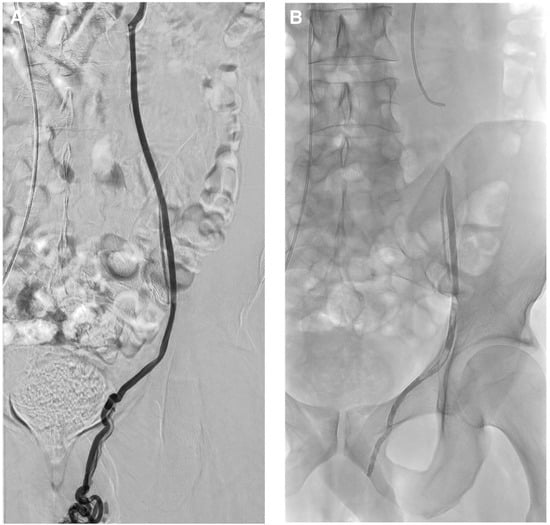

Figure 5. Superficial painful buttock arteriovenous malformation (AVM) in a 61-year-old patient. (A) Axial magnetic resonance imaging shows posterior subcutaneous contrast enhancement at the arterial phase, corresponding to the AVM. (B) Direct puncture of the nidus with a 21-gauge metallic needle and opacification of the nidus. (C) Embolization with a Glubran®2/Lipiodol® mixture of a 1:5 ratio. (D) Final result after complete embolization of the nidus.